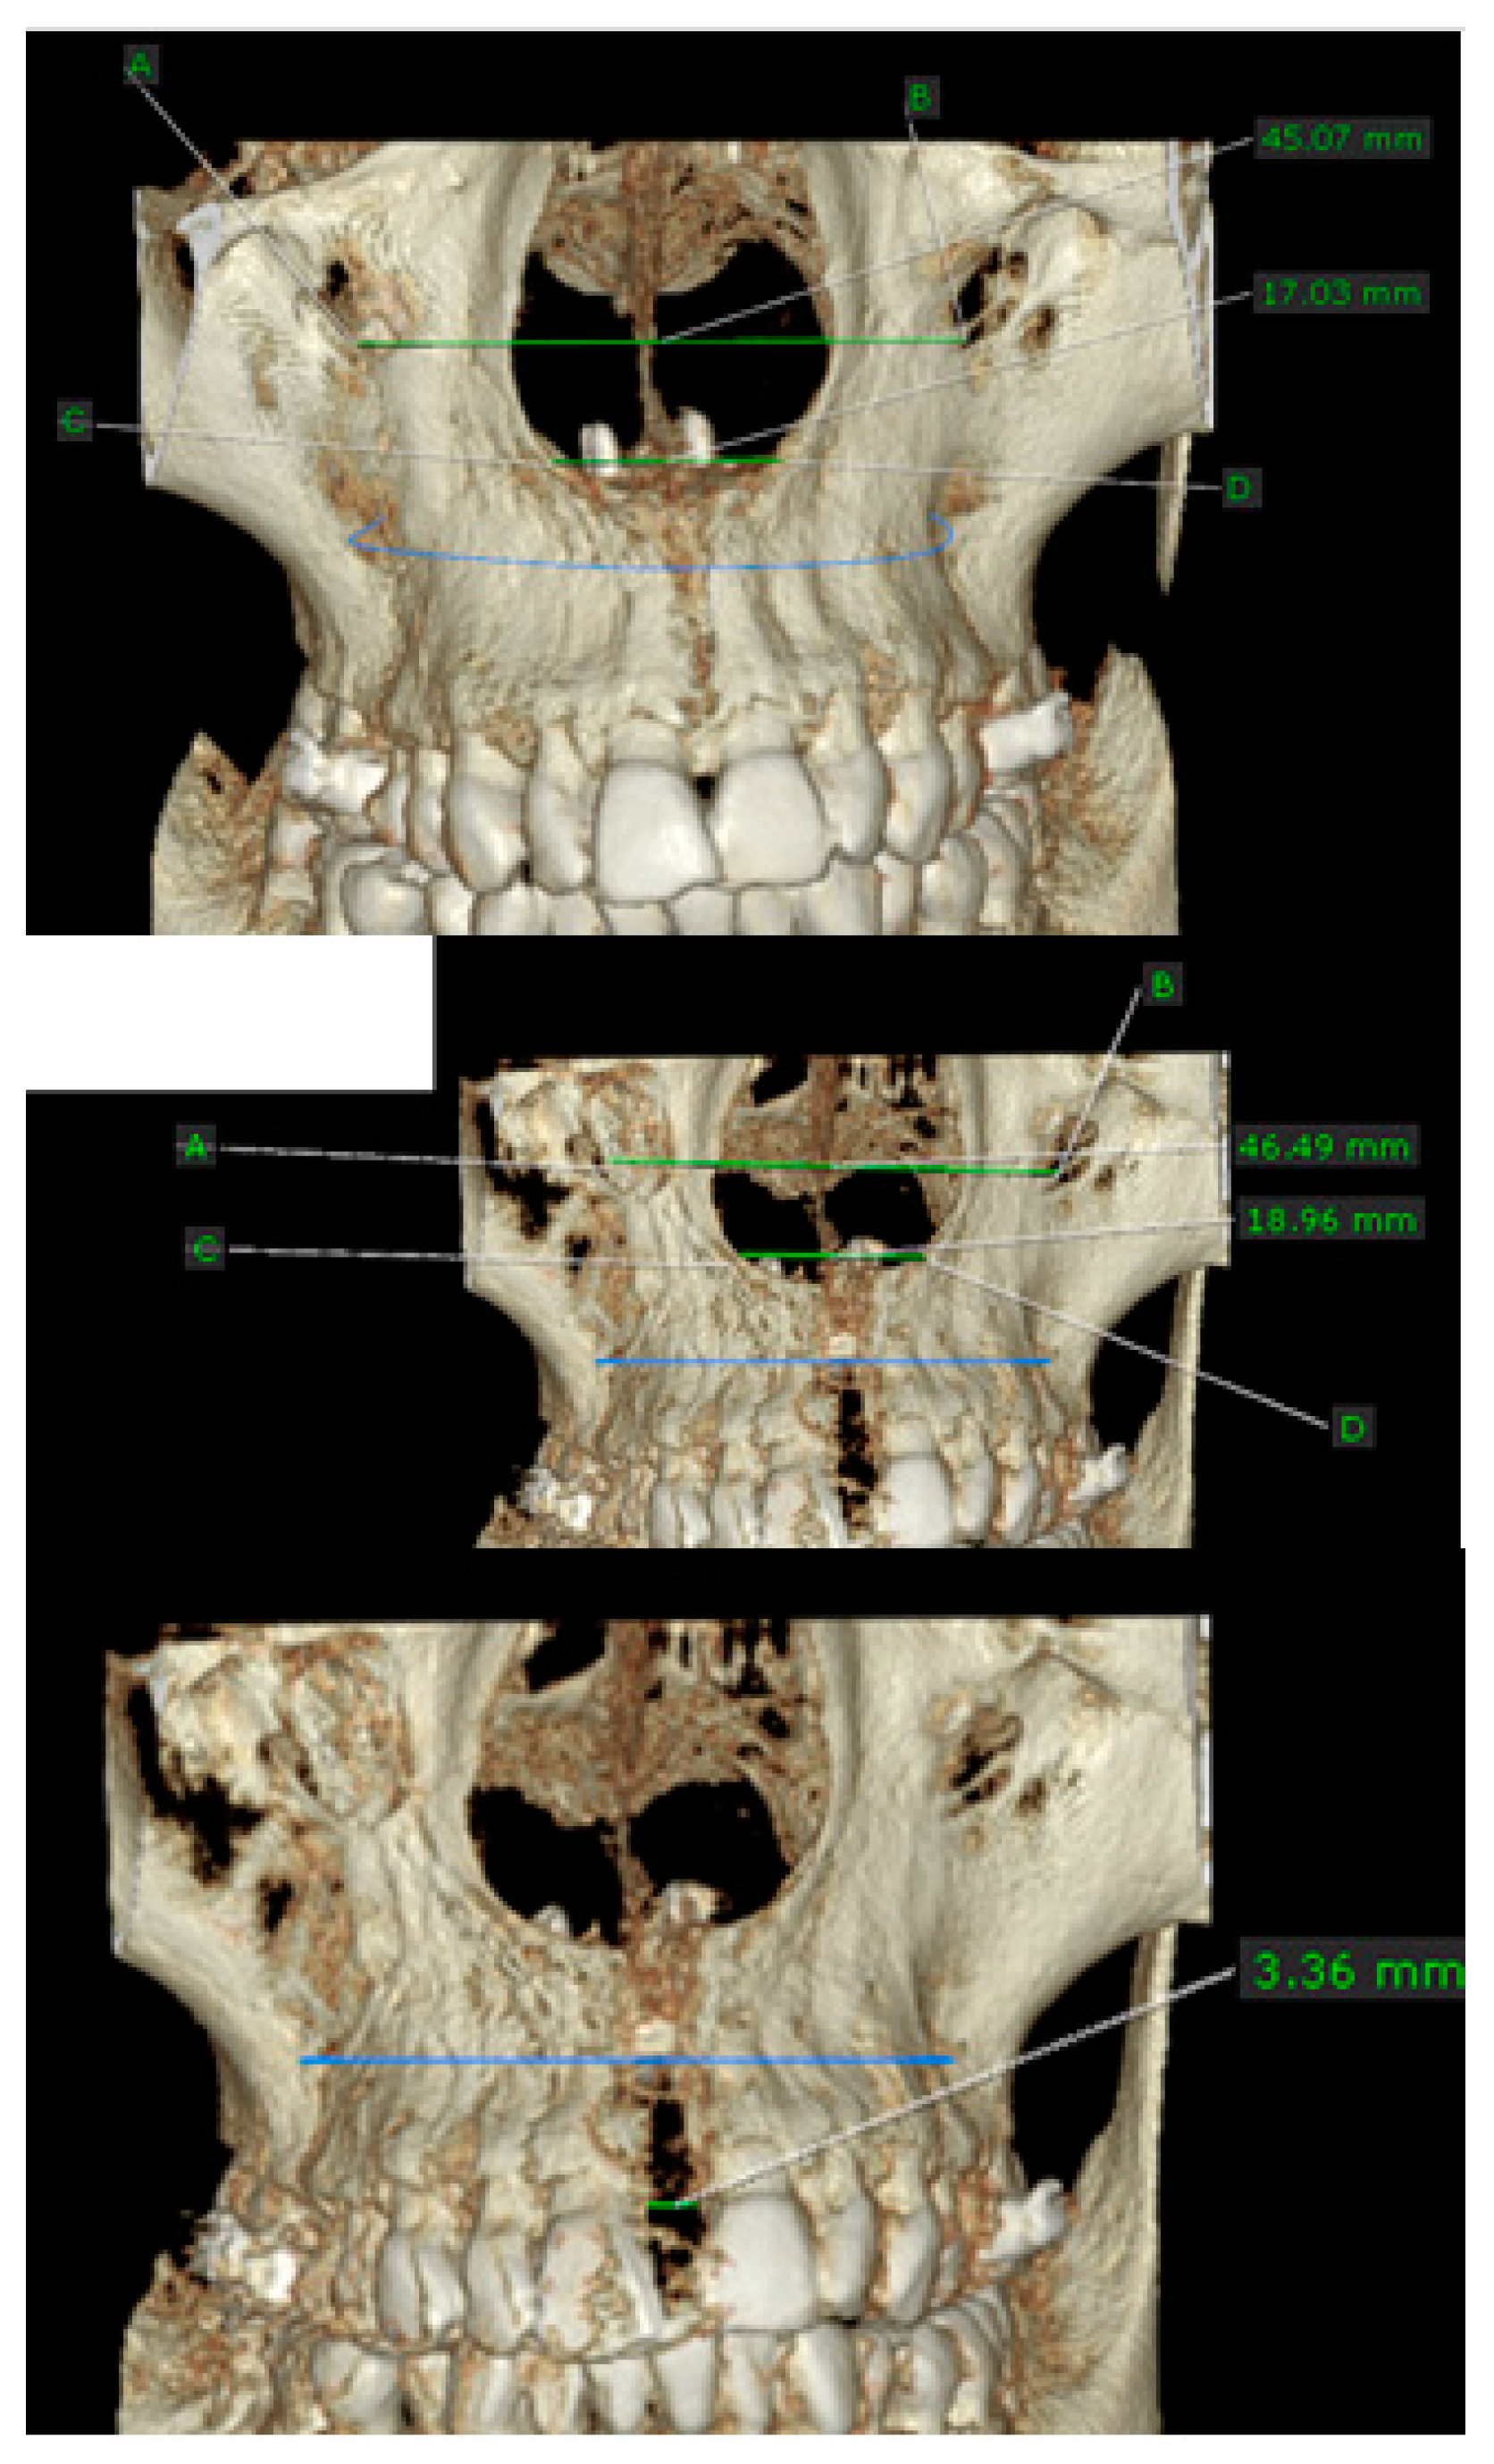

- MARPE associated with cortico-puncture therapy efficiently split the midpalatal suture in adults. The mean split at the anterior nasal spine (ANS) and posterior nasal spine (PNS) was 3.76 and 3.12 mm, respectively. The magnitude of the split at the PNS was smaller than at the ANS (by approximately 85% of the distance), showing that the opening of the midpalatal suture was almost parallel in the anteroposterior direction.

| Mean | 3.766 | 3.125 |

| Minimum | 3.360 |

| Mean | 4.103 |